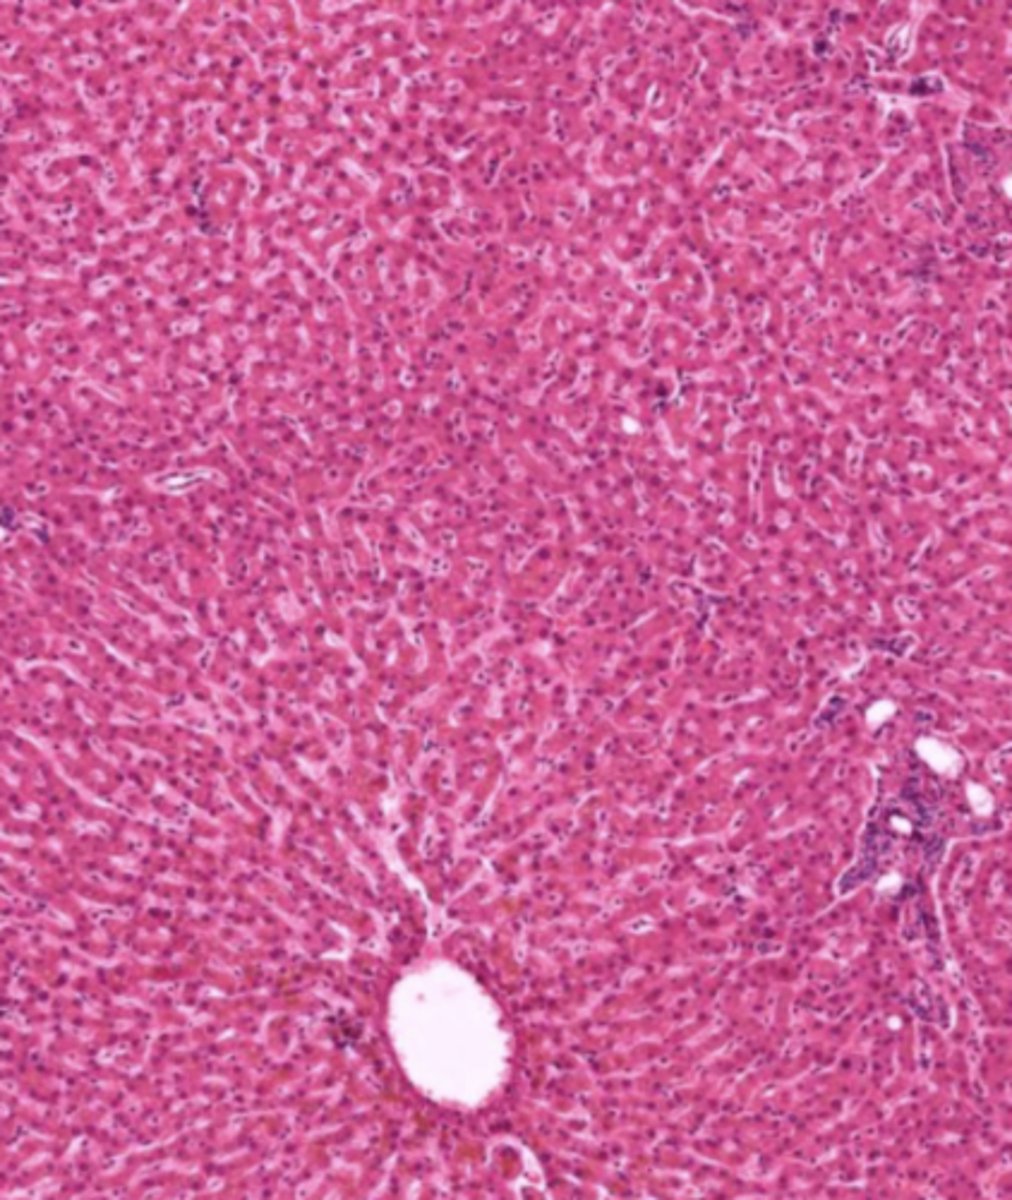

liver (histology)

hepatocyte (liver)